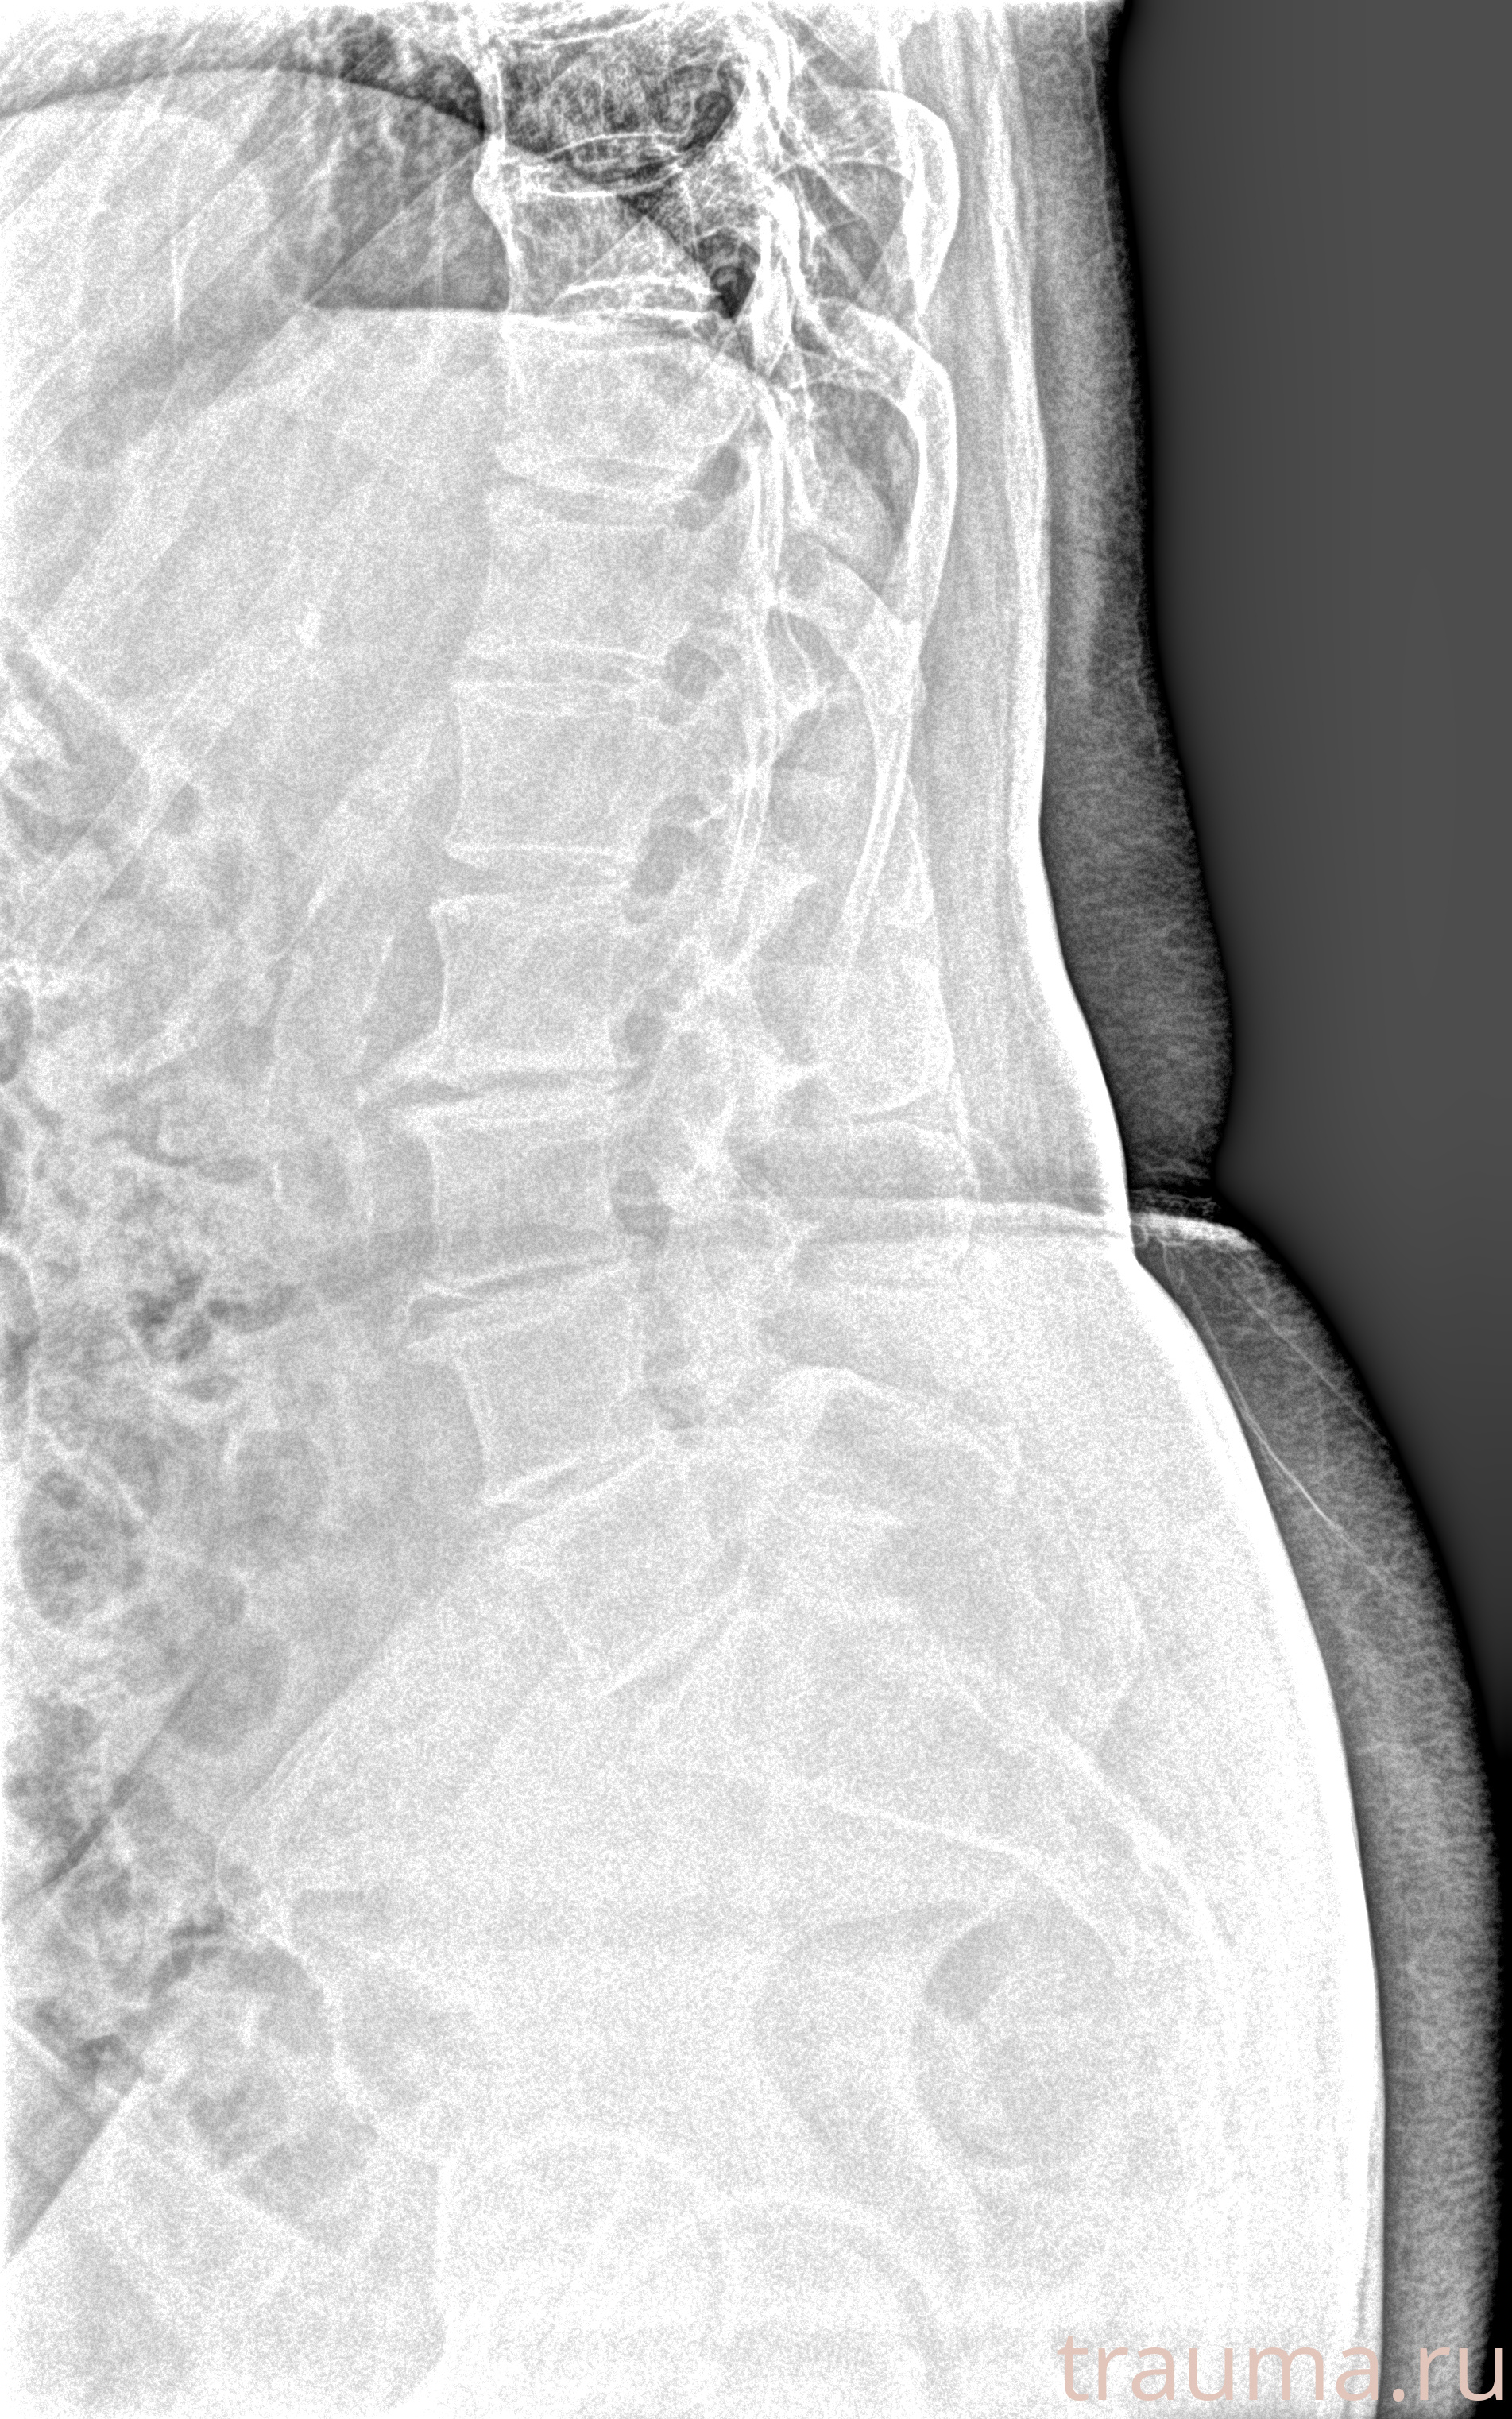

Рентген на дому: по вашему адресу приезжает врач-рентгенолог, травматолог-ортопед с мобильным рентгеновским аппаратом, проводит диагностику травмы или заболевания, делает необходимые рентгенограммы, дает рекомендации по дальнейшему лечению. Получить качественные снимки в домашних условиях возможно благодаря уникальной методике, разработанной МосРентген Центром для института  Склифосовского

при переломе шейки бедра и пневмонии от компании МосРентген Центр - партнера Института имени Склифосовского